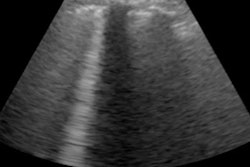

In a study published on May 27, Churchill and colleagues performed 125 echocardiograms requested by physicians on patients with COVID-19. More than two-thirds of patients (69%) were in the intensive care unit (ICU), and the vast majority of these patients required mechanical ventilation and vasopressor support.

More than one-quarter of patients in the study exhibited left ventricular dysfunction, including 22% of patients with impaired left ventricular ejection fraction and 14% of patients showing wall motion abnormalities.

However, left ventricular dysfunction also appeared to resolve for many patients as their COVID-19 symptoms improved. When the authors performed follow-up echocardiograms on 11 patients, 88% showed resolved abnormalities without procedural intervention. Only two patients showed persistent left ventricular dysfunction, and one of those patients had preexisting left ventricular dysfunction.

A second letter published on June 5 studied myocardial injury in 110 patients hospitalized consecutively with COVID-19 at Mount Sinai Icahn School of Medicine in New York City. The authors, led by Dr. Karan Sud, used portable ultrasound machines, with scans interpreted by board-certified echocardiography attending physicians.

A total of 37% of hospitalized patients with COVID-19 had isolated left ventricular dysfunction, the team found. Another 17% of patients had right ventricular dysfunction, and 17% had biventricular dysfunction. Only 29% of patients had preserved biventricular function.

Significant myocardial injury was present in 24 patients, the authors noted. A little more than 40% of patients with myocardial injury required mechanical ventilation at the time of the ultrasound scan.

Out of the patients with myocardial injury, 54% had left ventricular dysfunction, and 46% had regional wall motion abnormalities. Another one-third of these patients also had the presence of more than trivial pericardial effusion.